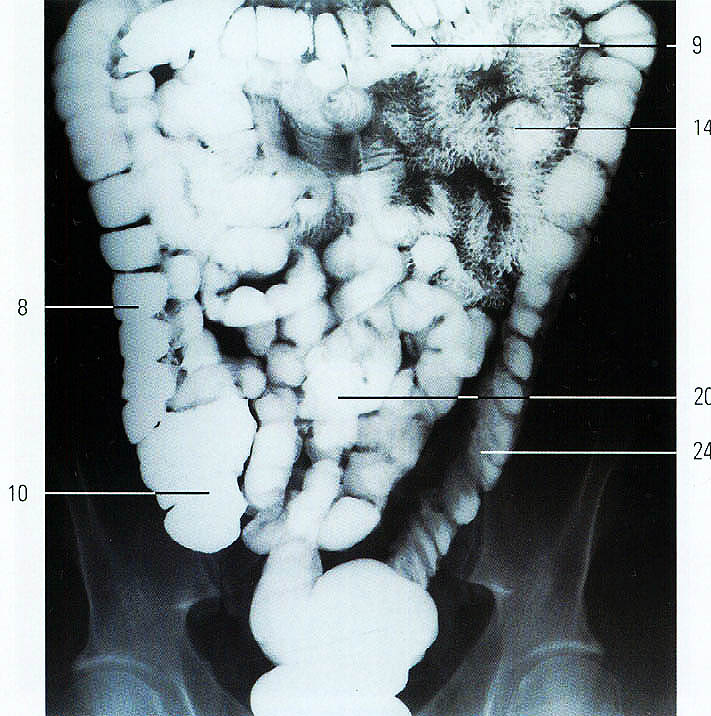

Нормы обзорной рентгенографии брюшной полости